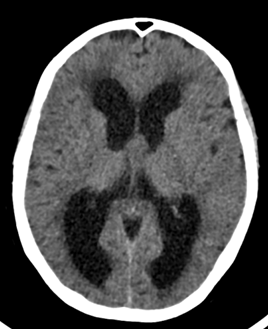

Se trata de un paciente de 63 años que comienza de forma subaguda con torpeza a la marcha y urgencia e incontinencia miccional. Acudió al servicio de urgencias donde se le realizó una TAC cerebral sin contraste (imagen 1 y 2) donde se observaba una hidrocefalia y se derivó a estudio ambulatorio con la sospecha de hidrocefalia normotensiva (imagen 2). La hidrocefalia se produce como consecuencia del aumento del líquido cefalorraquideo en el sistema ventricular cerebral o el espacio subaracnoideo.

En el estudio con resonancia cerebral se puso de manifiesto la existencia de un quiste coloide del III ventrículo que había pasado inicialmente desapercibido en la TAC cerebral.